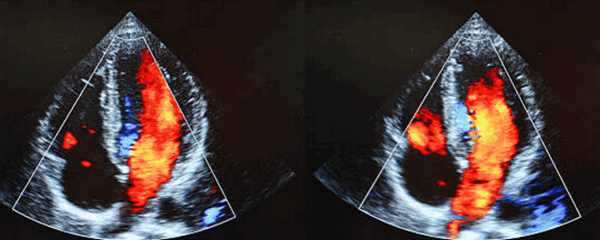

Несмотря на то, что этот врожденный порок сердца, который мы определяем на эхокардиографии, назван из-за поражения, связанного с ненормальным соединением и положением крупных артерий (аорта и легочная артерия), лучше рассматривать патологию как отклонение развития и положение желудочков. Эмбриональная петля желудочка у больных с врожденной корригированной транспозицией магистральных артерий является патологической. Это приводит к тому, что морфологически правый желудочек (ПЖ) формируется на левой стороне сердца и становится связанным с легочной артерией и легочными венами. Морфологически левый желудочек (ЛЖ) развивается на правой стороне сердца и становится связанным с легочной артерией и системными венами. Это обратное соединение предсердий с желудочками хорошо определяется на эхокардиографии и называется дискордантным расположением предсердий желудочков.

Хотя врожденная корригированная транспозиция магистральный артерий (КТМС) и полная транспозиция магистральных артерий имеют схожие названия, их анатомические и физиологические особенности очень различны. Несогласованные соединения, присущие КТМС, приводят к тому, что венозные потоки направляются в соответствующие артерии, но через «неправильные» желудочки. На эхокардиографическом исследовании видно, как неправильно размещен морфологически ПЖ, на анатомически ЛЖ, который, в свою очередь, вразнобой подключен к аорте. Справа соединения сердца точно так же неверные, к легочному венозному потоку, проходящему через легочную артерию, присоединен морфологически ЛЖ.